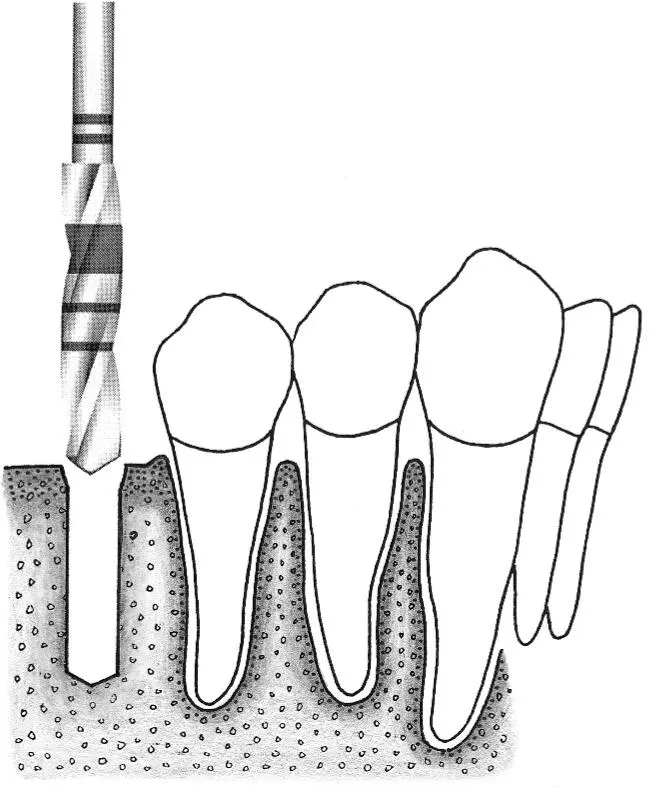

Fig 1-2Sequence of site preparation for a standard implant.

Fig 1-2a A no. 1 round bur is used to mark the position of the implant site.

Fig 1-2b Access is widened with a no. 2 round bur. This step makes it possible to correctly position the next drill.

Fig 1-2c The initial implant site preparation is made with a 2.2-mm-diameter pilot drill.